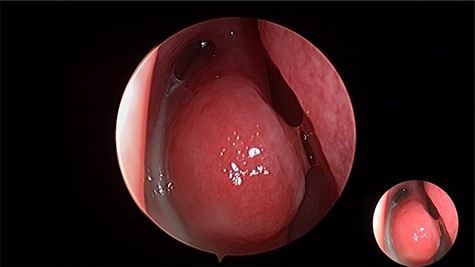

Intraoperative, the right middle meatus was full of frank pus (Fig. 2) which was drained. Endoscopic middle meatus antrostomies was performed and a bilateral big cystic masses completely filling both maxillary sinus were visualized along with a tooth impacted in the medial wall of the right maxillary sinus obstructing the natural drainage. The diagnosis of bilateral dentigerous cysts with ectopic teeth was made on clinical and radiographic findings.

Intraoperative endoscopic view of frank pus draining the right maxillary sinus